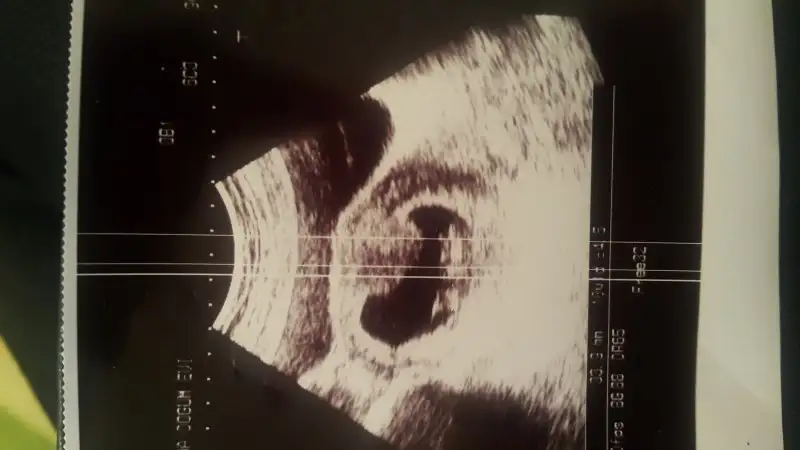

Plesenta sağda kız ama kesenin içindeki bebeğin konumunu pek anlayamadımbu usg de yorumlayabilir misiniz?

canım ilginc olanı bu usg aldıktan sonra ertesi gün başka bir doktora gittim ve kese çok farklıydı bak gönderiyorum. bir gün aralıkla farklı usg resimleri bir kız bir erkek mi olacak yaniPlesenta sağda kız ama kesenin içindeki bebeğin konumunu pek anlayamadım

Aaa evet burada erkek gibi plesentanın konumu Bebek erkek gibi burada ama ortada hiç belli olmazcanım ilginc olanı bu usg aldıktan sonra ertesi gün başka bir doktora gittim ve kese çok farklıydı bak gönderiyorum. bir gün aralıkla farklı usg resimleri bir kız bir erkek mi olacak yani

benimde kafam senin ki gibi karışık...yani ekranda gördügün gibi cıkmadı usg de dimi yani benim tek inandıgım doktor karnının hangi tarafından baktı? benim solumdan baktı ama usg resimi karnıma tutunca sagımda kalıyor:-/ keşke sana yardımcı olabilsem ama bende anlamıyorumkivilcim82 canım ben geçen hafta yani 6 hafta bitiminde ultrasona girdim karşımdaki ekranda bebeği sağa yapışık gördümm fakat doktor bana usg kağıdını verirken o noktayı büyütüp vermiş bu nedenle kağıtta hiç belli değil... Ben de heyecanlanıyodum alıcam burada paylaşıcam diye ama anlaşılır değil yani...